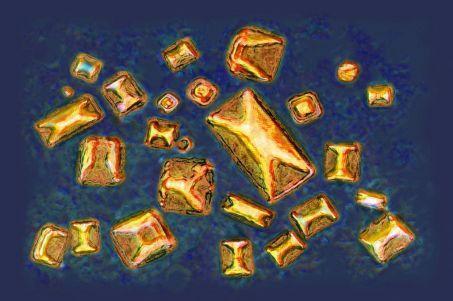

Les calculs rénaux sont des agrégats de cristaux qui se forment lorsque certaines substances présentes dans l’urine atteignent des concentrations suffisantes pour précipiter. Près de 80 % d’entre eux sont constitués d’oxalate de calcium, présent dans de nombreuses sources alimentaires comme le chocolat, le café (en grains), le thé,les fruits secs ou certains légumes feuilles notamment les épinards. Contrairement à un type rare de calculs infectieux déjà connu pour héberger des bactéries, ces calculs calciques étaient jusqu’à présent considérés comme strictement abiotiques.

Mais, en analysant des calculs d’oxalate de calcium à l’aide de microscopies électronique et de fluorescence, il a été mis en évidence la présence de bactéries vivantes, organisées en couches et en biofilms, intimement mêlées aux cristaux minéraux. « Ce résultat remet en cause l’idée selon laquelle ces calculs se formeraient uniquement par des processus chimiques et physiques », explique Kymora Scotland, professeure adjointe d’urologie à la David Geffen School of Medicine et co-autrice de l’étude, publiée dans les PNAS. « Nos données étayent l’hypothèse selon laquelle les bactéries favorisent la croissance et la stabilisation du calcul une fois sa formation commencée ».

Dans un article complémentaire, à paraître dans une autre revue, la même équipe indique que les bactéries jouent également un rôle dans la nucléation cristalline, c’est-à-dire à la première étape de la formation du calcul. Autrement dit, les calculs ne se forment pas seulement par assemblage passif de cristaux mais ils constituent un environnement structuré où les bactéries participent à leur édification et à leur consolidation. Cette interaction intime entre le vivant et le minéral pourrait expliquer en partie pourquoi les calculs d’oxalate de calcium sont si répandus. Elle suggère aussi que leur résistance aux traitements et leur tendance à récidiver ne relèvent pas uniquement de la chimie urinaire ou de l’alimentation.